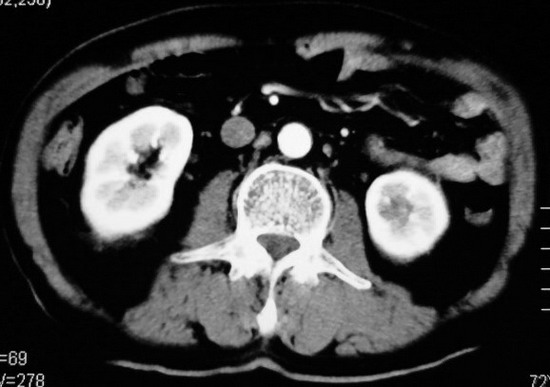

以下是引用杀毒软件在2008-11-17 19:15:00的发言:[br]考虑------右肾癌合并肾静脉---同侧肾上腺受侵可能性大

以下是引用zjzjr在2008-11-17 20:45:00的发言:[br]考虑------右肾癌合并肾静脉---同侧肾上腺受侵可能性大及腹膜后淋巴结转移.